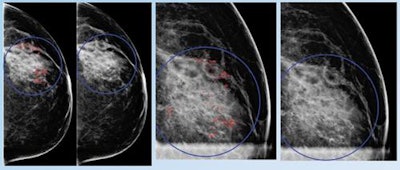

In a series of studies presented at ECR 2017 earlier this month and at RSNA 2016, researchers led by Dr. Alyssa Watanabe of the University of Southern California (USC) Keck School of Medicine shared how deep learning can yield higher sensitivity and specificity for both breast masses and calcifications, compared with traditional mammography CAD techniques, even identifying cancer in some cases years before radiologists did.

They also reported that the deep learning-trained CAD software could differentiate benign and malignant breast calcifications better than radiologists could on their own, offering the promise of sharply reducing the number of negative biopsies.

To see if the deep learning-trained CAD software could help avoid some of these unnecessary biopsies, the researchers used an enriched dataset of 391 mammograms with biopsy-proven calcifications (302 benign and 89 malignant) provided by two institutions: a community-based imaging practice and an academic radiology department. They then compared the CAD software's performance with the biopsy recommendations previously provided by the fellowship-trained breast imaging radiologists at the two sites.